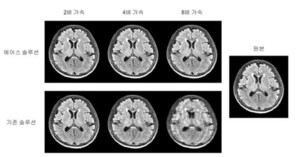

- 서울대 공대 대학원생들, MRI 촬영시간 단축 기술 개발

- [대학저널 임지연 기자] 서울대학교 공학대학(학장 차국헌) 대학원생들이 자기공명영상(MRI) 촬영에 소요되는 시간을 획기적으로 줄일 수 있는 기술을 개발했다. 이 기술은 현재 MRI 장비에 바로 적용 가능하다.서울대 공대 전기정보공학 ...